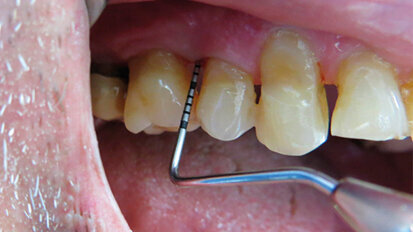

L’utilizzo della terapia fotodinamica HELBO nella parodontopatia

Un valido aiuto nel combattere il biofilm batterico, causa dei principali insuccessi nel trattamento sia della parodontite sia della perimplantite, viene ...